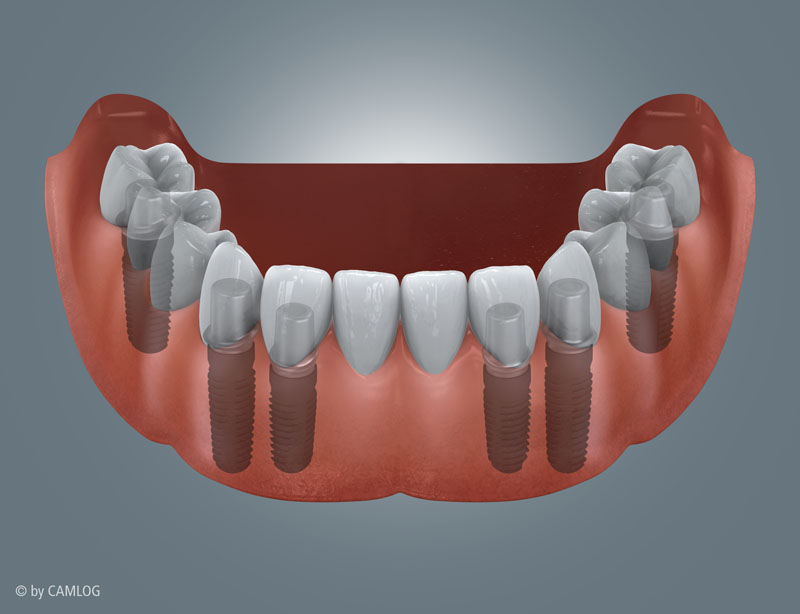

Zahnloser Unterkiefer mit Brückenversorgung